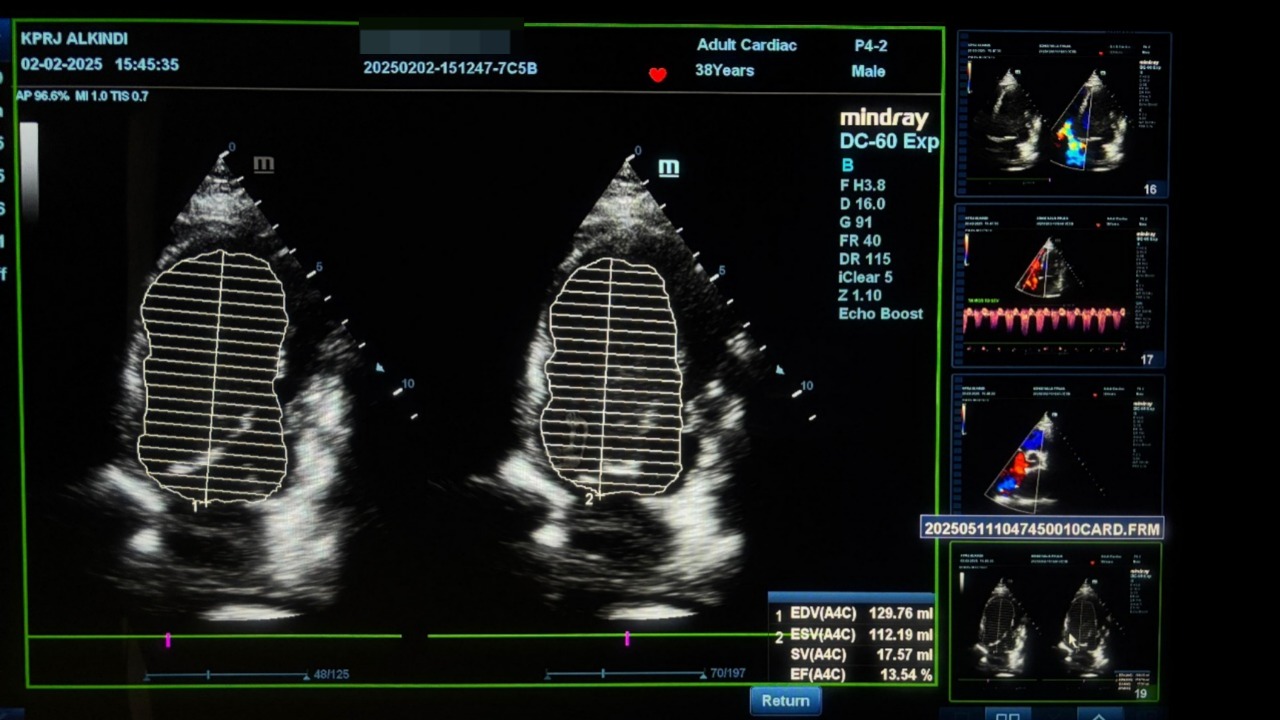

KASUS KLINIS: “ seorang laki-laki 38 Tahun, datang dengan keluhan sesak berat, mudah lelah, dan tidak bisa tidur telentang, Sudah direkomendasikan untuk operasi Jantung .dengan EF atau pompa jantung 13.54% , menyebabkan akumulasi cairan pada kantung paru , kantung perut dan kedua kaki Setelah pasien memilih mengikuti program CardiacSave didapati hasil perbaikan yang significant Pemantauan ketat via echocardiography, lab jantung, dan EKG

Sebelum terapi Program Cardicasave

Pada pemeriksaan Echocardiografi didapati EF hanya 13,54% (02-02-2025)

Menandakan pompa jantung sangat lemah, risiko kematian tinggi, dan kemungkinan sel-sel jantung sudah mengalami kerusakan karena iskemia (kekurangan oksigen akibat sumbatan koroner).